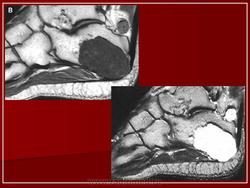

Хондрома.

Хондрома.